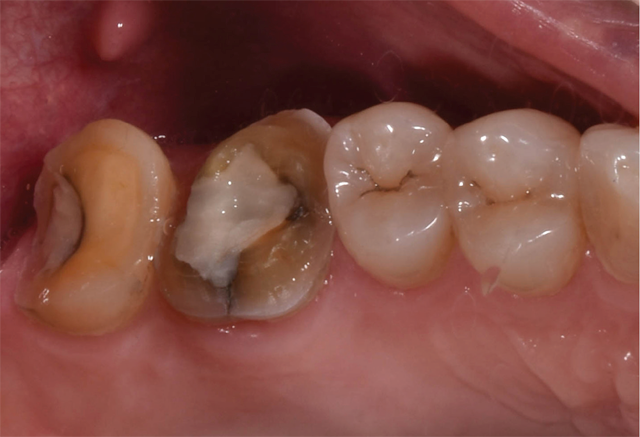

The prepared teeth and buccal bite were then scanned using the Planmeca Emerald. A detailed examination of the preparation design, including margin placement and occlusal clearance, was performed on the PlanScan system monitor. A shade was selected using the Ivoclar Vivadent e.max CAD shade guide. Once satisfied with the preparations, the margins were easily marked and the restorations were designed, taking into account necessary material thickness, contacts, embrasures and occlusion (Figs. 3 and 4). Sprue placement was verified and the designs were sent to the mill.

Fig. 3 Fig. 4